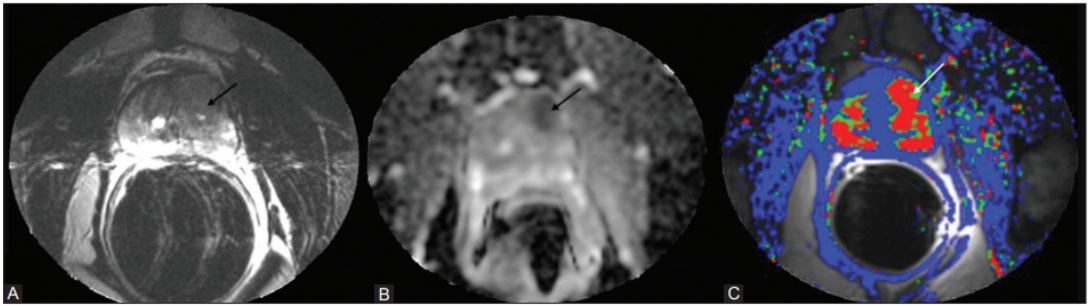

ADC value/diffusion restriction: On diffusion-weighted imaging, cancer often appears as “restricted diffusion” with a low apparent diffusion coefficient (ADC), reflecting tightly packed cells14. Benign tissue usually has higher ADC values and less restriction15.

Most clinically important prostate tumours are adenocarcinomas. On MRI, they tend to be dark on T2, show restricted diffusion (low ADC), and often enhance early with contrast, but appearances vary by zone, grade, and size26.

Most prostate cancers are acinar adenocarcinomas arising in the peripheral zone; on mpMRI, these usually appear as focal, round or oval low-signal areas on T2-weighted images, with marked diffusion restriction and corresponding low ADC values27.

Clinically significant cancers (higher grade, larger volume) tend to show more pronounced diffusion restriction, with very low ADC and very bright high-b-value DWI signal, and more conspicuous, early contrast uptake on dynamic imaging30. These lesions are more likely to be scored PI-RADS 4-5 and correlate with higher Gleason/ISUP grades on biopsy.

mpMRI combines at least three components: high-resolution T2-weighted images for anatomy, DWI/ADC for cell density, and dynamic contrast-enhanced (DCE) imaging for vascularity32. This protocol is still the reference standard in many centres because it improves confidence in calling a lesion benign vs clinically significant, and it underpins PI-RADS.